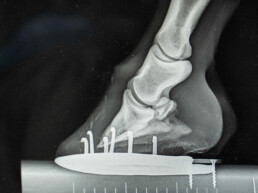

Bildgebung und weiterführende Diagnostik

Mit modernen diagnostischen Verfahren wie Ultraschall und digitalem Röntgen verschaffe ich mir ein genaues Bild vom Gesundheitszustand Ihres Pferdes und leite gezielt die passende Behandlung ein.

• Digitales Röntgen (Gliedmaßen, Kopf, Zähne, Wirbelsäule)